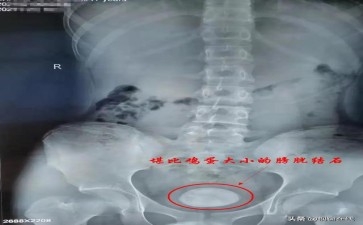

膀胱 “尿液蓄水池” 咋长出 “水底暗礁”?在人体这座复杂的 “生命城市” 里,膀胱就像储存尿液的 “巨型蓄水池”,协调着尿液排出的节奏。可当膀胱结石出现,就如同蓄水池底部悄然长出了尖锐的 “暗礁”,看似平静的水面下,藏着随时可能引发 “翻船事故” 的危机。

这些 “捣乱暗礁” 的形成,和 “蓄水池” 的 “异常运作” 紧密相连。长期憋尿,好比让蓄水池的水长期停滞,杂质更容易沉淀;饮水过少,就像只往池里倒脏水却不及时补充清洁水源;前列腺增生、尿道狭窄等问题,则如同蓄水池的排水口被堵住,水流不畅导致杂质堆积。起初,小结石只是池底的细小砂砾,随着它们不断聚集变大,排尿时的疼痛、血尿就像船只撞上暗礁发出的刺耳警报,尿流中断等 “运输故障” 也会频繁出现,严重时甚至可能损伤膀胱内壁,影响整个 “城市” 的正常运转。